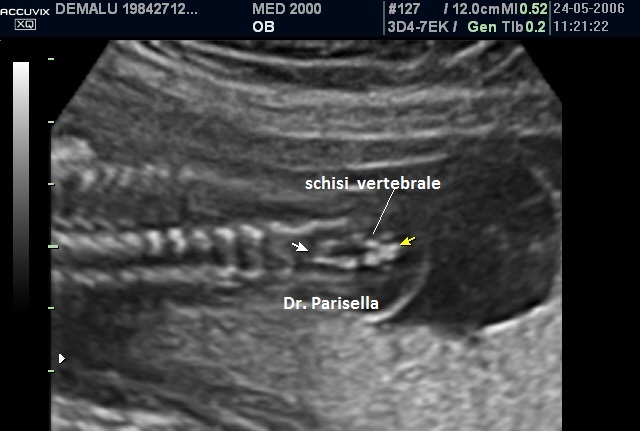

4) schisi vertebrale;

5) mielomeningocele: formazione cistica settata sovrapposta alla schisi vertebrale.

E' opportuno fare una precisazione importante, utile anche ai fini medico legali: nonostante l'esperienza degli operatori e l'utilizzo di apparecchiature sempre più sofisticate, la valutazione ecografica della colonna vertebrale è a tutt'oggi ancora piuttosto difficoltosa per cui la diagnosi ecografica della spina bifida si basa fondamentalmente sulla presenza dei segni indiretti; infatti questi hanno una sensibilità sicuramente maggiore, rispetto ai segni diretti, nel sospettare la presenza di questa malformazione.